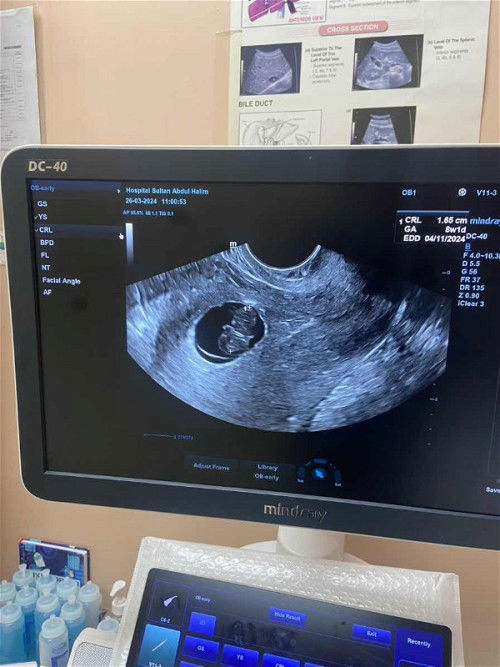

Janin tiada detak jantung

Rasa susah hati sebab dh 8 weeks 1 day tapi tiada detak jantung.. doc tak ckp apa hanya suruh tunggu lgi 3 minggu sebab janin membesar dgn baik cuma tiada jantung lagi..cuma saya ada spotting brown 2 minggu lepas lalu smpai sekarang.. mintak ubat utk kuatkn rahim doc tk bg sbb tiada jantung dia kata.. klau ada mereka akan bagi😭ada ka moms yg detak jantung baby lambat ? ##firstmom firstmom #bantujawab #newmom #bantusharing